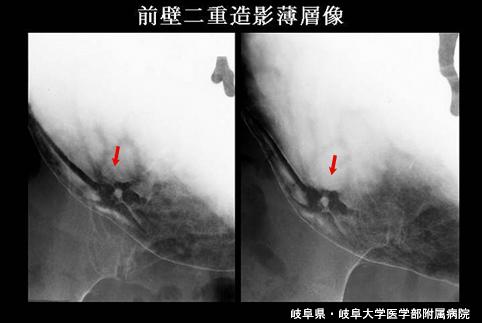

症例提示(所在地,施設名等): 岐阜県・ 岐阜大学医学部附属病院 (Dr.後藤ら)

疾患(病理主体)の分類悪性上皮性腫瘍/腺癌

部位(臓器別)胃(部位)/体部

検査方法X-P

腫瘍の肉眼分類0型(表在型)/IIa型(IIa+IIc)

病変の最大径(ミリ)10〜14

腫瘍の深達度sm